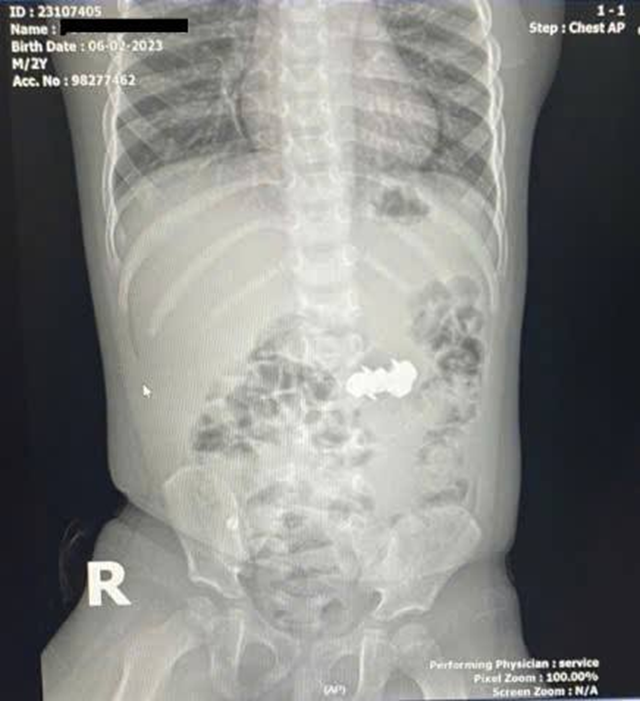

Bé D.H.P. (2 tuổi, trú tại Nghệ An) được gia đình đưa đến viện trong tình trạng nghi ngờ nuốt dị vật trong lúc chơi đồ chơi. Kết quả chụp X-quang bụng cho thấy trong ổ bụng có bốn dị vật kim loại nhỏ hình tròn, có đầu nhọn, nghi là đinh nam châm. Các viên nam châm này đã hút dính nhau trong đường tiêu hoá, tạo nên nguy cơ đặc biệt nghiêm trọng.

Tại Khoa Cấp cứu tổng hợp, các bác sĩ tiến hành thăm khám lâm sàng và chỉ định các cận lâm sàng cần thiết, trong đó có thực hiện chụp X-Quang có cản quang vùng bụng.

Hình ảnh ghi nhận có dị vật cản quang dạng chuỗi nằm ở vùng bụng quanh rốn và hố chậu phải. Các bác sĩ đã hội chẩn liên khoa và thống nhất thực hiện phẫu thuật nội soi ổ bụng cấp cứu.